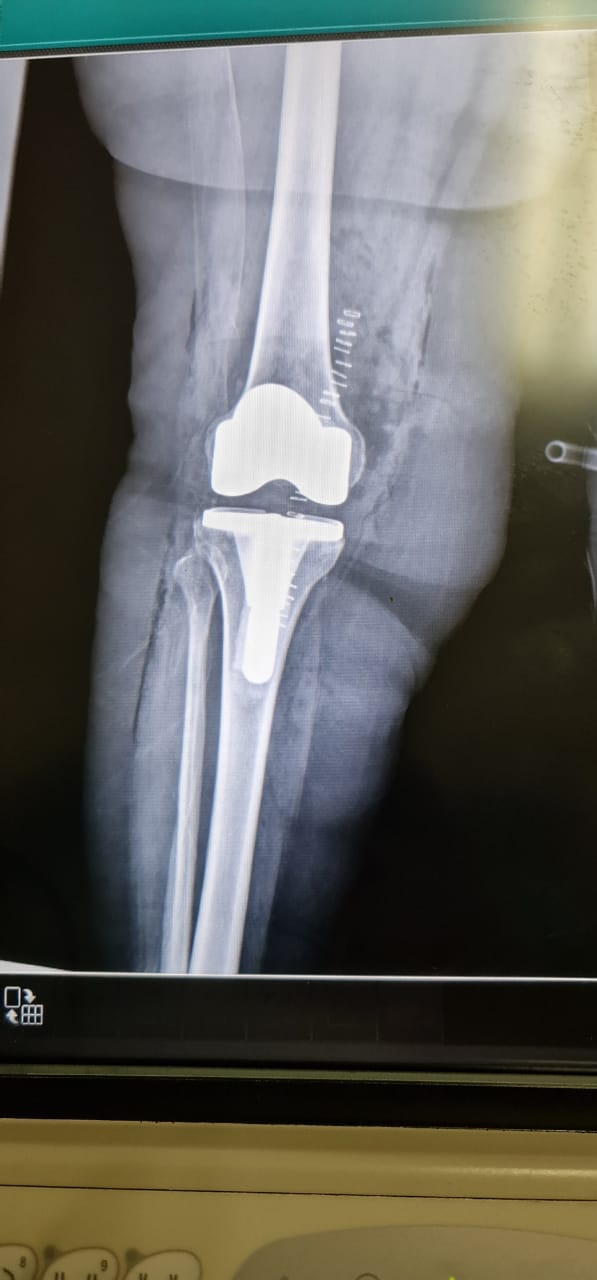

حيث تم إجراء عملية معقدة بقيادة استشاري جراحة العظام واستبدال المفاصل والطب الرياضي والمناظير الدكتور/ يوسف بن توفيق خوجة لإستبدال مفصل الركبة بالمفصل الصناعي تحت تخدير نصفي ، و وعي كامل للمريضة وتكللت العملية بالنجاح وبدون حدوث مضاعفات ، حيث تمكنت المريضة من المشي بعد العملية بساعتين وخروجها من المستشفى بعد يومين من إجراء العملية وهي في حالة مستقرة ولله الحمد.